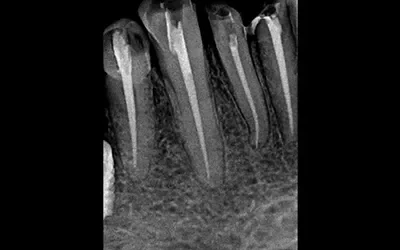

Is The Root Canal Treatment Painful: Let’s Take The Pain Out Of It

You have been recommended to get a root canal treatment by your Dentist (Or google??) to save your tooth and remove the infection, but it has started giving you sleepless nights. Let’s get our facts RIGHT… Few years back the root canal was the baddie of dentistry,...